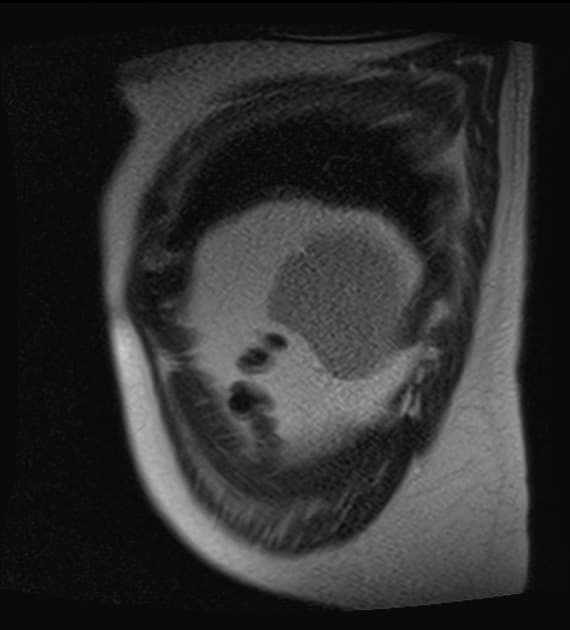

Axial T2

MRI•Axial T2•1 / 26

- Thấy một tổn thương tăng tín hiệu trên T1, giảm tín hiệu trên T2 (T1 hyperintense, T2 hypointense), khu trú tại thùy đuôi gan, có hạn chế khuếch tán ở vùng trung tâm (central restricted diffusion) và không có tăng quang đáng kể sau tiêm thuốc cản quang (no significant post-contrast enhancement).

- "Xuất huyết trong tổn thương u tuyến gan có thể biểu hiện tăng tín hiệu trên T1, giảm tín hiệu trên T2 và hạn chế khuếch tán."

Xuất huyết vào u tuyến gan là một biến chứng nghiêm trọng tiềm tàng của khối u gan lành tính, thường liên quan đến việc sử dụng thuốc tránh thai đường uống kéo dài. Hình ảnh học thường cho thấy tổn thương tăng tín hiệu trên T1, giảm tín hiệu trên T2 do methemoglobin trong xuất huyết bán cấp, với mức độ tăng quang thay đổi. Việc không thấy mỡ trên hình ảnh out-of-phase và không tăng quang đáng kể giúp phân biệt với các khối ác tính như ung thư biểu mô tế bào gan. Việc xác định chẩn đoán cần kết hợp lâm sàng, đặc biệt là tiền sử sử dụng hormone. Quản lý có thể bao gồm ngưng thuốc tránh thai, theo dõi định kỳ hoặc cắt bỏ ngoại khoa tùy theo kích thước, triệu chứng và nguy cơ vỡ.